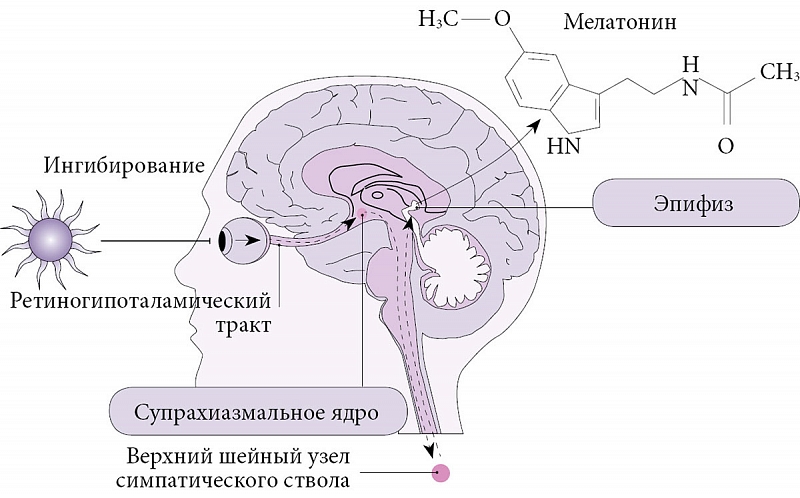

Как работает центр насыщения в гипоталамусе: визуальные иллюстрации